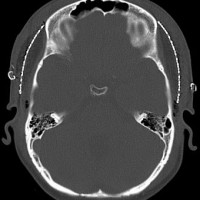

全脳照射後の頭蓋骨の部分的発育不全

2歳くらいで全脳照射を受けた子どもが15歳になりました。前頭骨だけの発育が悪くて額の間がとても狭くて,コメカミの凹みが目立つようになりました。両側の側頭部にチタンプレートを入れて額を広くして頭蓋形成をして,見栄えはとても良くなりました。このような手術を整容的頭蓋形成術といいます。